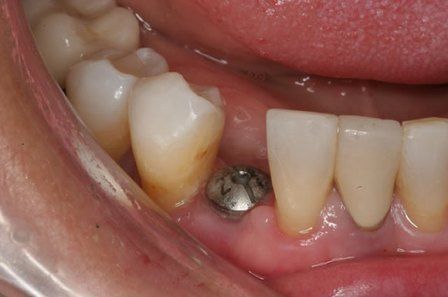

Endosteal implantlar - bu implantlar, cerrahi yöntemle, çene kemiğine direkt olarak implante edilirler. Çevredeki dişeti dokusu iyileştikten sonra, orijinal implanta bağlantı sağlayacak materyali takmak için ikinci bir operasyon gerekir. Son olarak, yapay diş (veya dişler) tek başına veya köprü ya da protez üzerinde grup halinde implanta takılır.

İMPLANT DİŞLERİ DOĞAL GÖRÜNÜR MÜ? İmplant kemik ve dişeti altında yerleşmektedir. Bu sebeple üstüne yapılan dişle herhangi bir uyumsuzluk söz konusu olmamaktadır. Özellikle son dönemlerde gelişen zirkon üst yapılar sayesinde ön bölge estetiğinde bile tam bir uyum sağlanmaktadır.

İMPLANTLARIN YERLEŞTİRMESİ VE PROTEZ KADAR SÜRER? Cerrahi işlemin süresi yerleştirilecek implant sayısına ve hastanın koşullarına bağlı olarak yarım saat ile birkaç saat arasında değişebilir. Operasyondan sonra, implant ile kemiğin kaynaşması için (osseointegrasyon) 2-3 ay kadar beklenir. Daha sonra bu implantlar üzerine, birkaç seans süren bir uygulama ile protezler yerleştirilir. İmplantlar dişler çekildikten hemen sonra yerleştirilebilir mi? Evet,günümüzde bu mümkündür.İmplant diş çekimini takiben taze çekim boşluğu içerisine yerleştirilebilir.Buna “immediyat uygulama” denir.